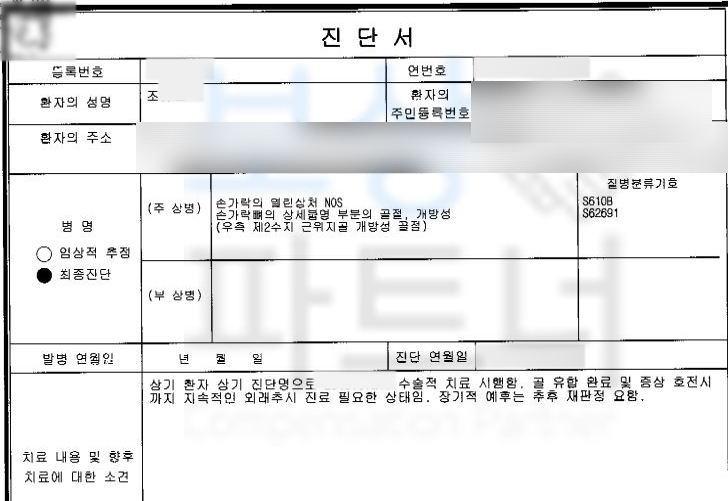

조@@님은 공사 현장에서 자재가 손가락 위로 떨어져 검지손가락이 골절되는 재해를 당하셨습니다. 진단서도 함께 보실까요?

진단서 상의 NOS는 상세불명을 의미하고, 중요한 것은 우측 제2수지 근위지골 개방성 골절 위 진단으로 인해 조@@님은 금속 고정술 즉 핀 고정을 하는 수술적 치료를 받으셨어야 했습니다.